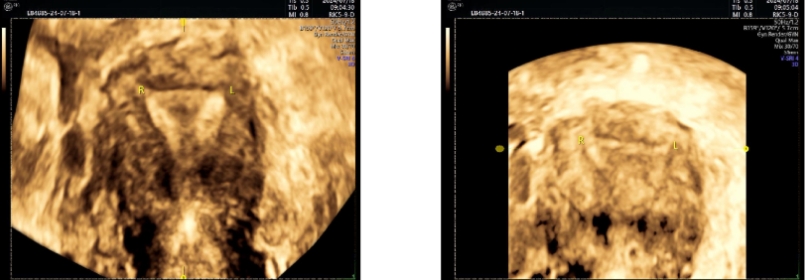

一位处于育龄阶段的女性,其健康状况让人担心。2024年5月24日,是她最后一次来月经的日子。在月经第20天的时候,做了四维彩超,结果显示出不少问题。内膜厚度不均匀,下段大约是2.3mm,中段约为3.1mm,上段约4.7mm。内膜的这种情况不太好,这为后续的诊断以及治疗埋下了隐患。

原来,这位患者在2024年1月的时候,曾在外院做过宫腔镜下宫腔粘连分离术,手术过程中还进行了上环术。然而此次通过四维彩超检查,又发现存在宫腔粘连的可能性,以及宫内节育器下移并嵌顿的可能性。另外,她有剖宫产手术史,由此形成了瘢痕子宫,她在2014年做过剖宫产术,2023年因为脑干胶质瘤出现了特殊情况,不良孕产史给治疗增加了复杂性。

此次检查发现了其他病症,除了之前提到的宫腔粘连和节育器问题。四维彩超显示,子宫后壁下段有稍高回声结节,怀疑是子宫腺肌瘤。子宫前壁下段有低回声结节,考虑是子宫肌瘤(5型)。诊断已经明确,病情比较复杂,多种病症同时存在。